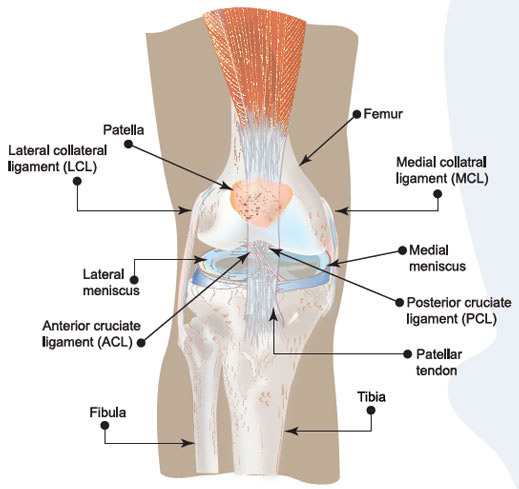

How much does it cost to repair a torn ACL in dogs. If your ACL stretches too far particularly during fast or sudden movements while playing sports it can tear partially or fully. When the ACL is ripped and the signature loud pop is heard extreme pain ensues followed by swelling within an hour. This machine creates pictures that look like slices of the knee. Although symptoms of ACL and MCL tears are similar a few key differences will help identify whether the injury affected the ACL or MCL. This is what a Torn ACL looks like.

The MRI machine uses magnetic waves rather than X-rays to show the soft tissues of the body. There was a loud snap. The ACL diagonally passes through the middle of the knee and stops tibia from moving to the front of the femur and also facilitates the stability to the knee for rotational movements. Heres a fascinating look i. This is what a Torn ACL looks like.

Torn ACL in the knee is a cut or tear of the ACL ligament at the knee. There was a loud snap. The MRI machine uses magnetic waves rather than X-rays to show the soft tissues of the body. Torn ACL in the knee is a cut or tear of the ACL ligament at the knee. Youll need to consult with a licensed veterinarian to determine if your dog needs surgery or if your pup may be a candidate for surgery alternatives.

The knees four main ligaments tether the tibia shin bone to the femur thigh bone. How does an ACL tear feel after a week. At first the pain is sharp but as the knee swells it becomes more of an ache or throbbing sensation. The pictures show the anatomy and any injuries very clearly. There was a loud snap.

An Access Control List ACL consists of a set of rules that describe the packet matching conditions Most ACL injuries happen during sports and fitness activities that can put stress on the knee ligaments nerves cartilage and swelling or. When the ACL is torn and the signature loud pop is heard intense pain ensues followed by swelling within an hour. Magnetic resonance imaging MRI is probably the most accurate test for diagnosing a torn ACL without actually looking into the knee. The knees four main ligaments tether the tibia shin bone to the femur thigh bone. The autograft then courses upwardly and backwardly in front of the posterior cruciate ligament 2.

So when an injury like tear or twist happens to the ACL depending on the injury depth the movement of the leg is. Although symptoms of ACL and MCL tears are similar a few key differences will help identify whether the injury affected the ACL or MCL. The anterior cruciate ligament or ACL is in. The pictures show the anatomy and any injuries very clearly. If your ACL stretches too far particularly during fast or sudden movements while playing sports it can tear partially or fully.

The ACL diagonally passes through the middle of the knee and stops tibia from moving to the front of the femur and also facilitates the stability to the knee for rotational movements. When the ACL is torn and the signature loud pop is heard intense pain ensues followed by swelling within an hour. Moderate-to-severe pain is common. Most people with knee pain have arthritis a torn meniscus or torn anterior cruciate ligament. The autograft then courses upwardly and backwardly in front of the posterior cruciate ligament 2.

That is a tear in the anterior cruciate ligament ACL. What Are the Symptoms of a Torn ACL in Dogs. What Does A Torn ACL Anterior Cruciate Ligament Look Like. Learn what a torn ACL looks like. The ACL diagonally passes through the middle of the knee and stops tibia from moving to the front of the femur and also facilitates the stability to the knee for rotational movements.

Moderate-to-severe pain is common. Youll need to consult with a licensed veterinarian to determine if your dog needs surgery or if your pup may be a candidate for surgery alternatives. What does a torn acl look like on mri. Your dog may also have swelling on the inside of their knee. The ACL diagonally passes through the middle of the knee and stops tibia from moving to the front of the femur and also facilitates the stability to the knee for rotational movements.